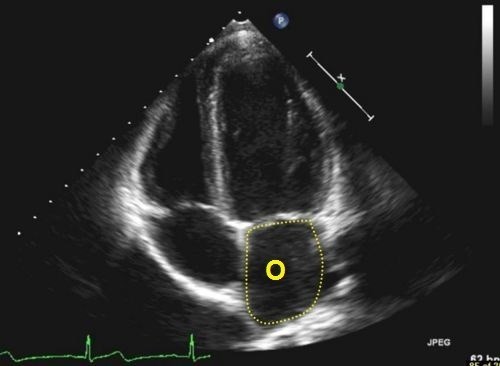

A dál co potřebujete k získání finálních souřadnic? Trocha z té zdravotnické praxe. Správný geokačer má silně vyvinutý smysl pro všímání si detailů, skrytých souvislostí a tak podobně. Princip je jednoduchý. Nepůjde o žádnou kdoví jak složitou matematickou šifru s IT podtextem. V budoucích několika minutách, hodinách či dnech se z Vás stanou radiologové (lékaři zabývající se zobrazovacími technikami) a anatomové. Tak Vás jistě nepřekvapí několik obrázků, na kterých bude vyznačen útvar, který musíte poznat a latinsky (pokud jiným jazykem, tak Vás na to upozorním) pojmenovat. Myslím, že vše bude jasné. Tak jdeme na to…

O - počet písmen v názvu útvaru (latinsky, 2 slova)